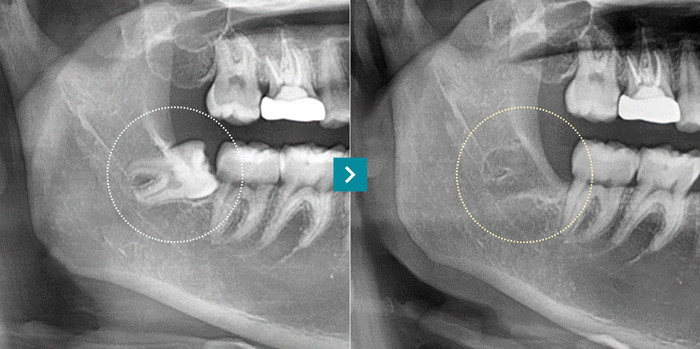

Comparison before and after wisdom tooth extraction